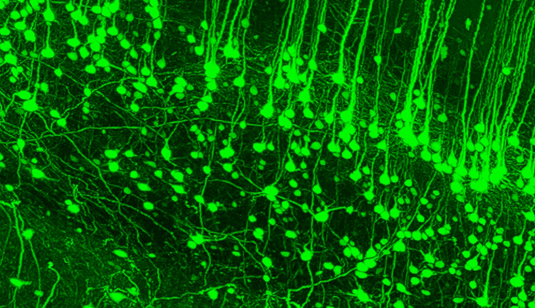

Strutture neuronali a risoluzione subcellulare nella corteccia.Una tecnica di imaging nuova e versatile consente ai ricercatori di tracciare le traiettorie di intere cellule nervose e fornisce molte informazioni sulla struttura delle reti neuronali.

Perciò i danni a questi assoni possono influenzare la funzione di parti del sistema nervoso centrale che sono lontani dalla sede effettiva della lesione. Il nuovo metodo di imaging si basa su una procedura di clearing-and-shrinkage (schiarimento-e-riduzione) che può rendere trasparenti interi organi e organismi, rendendo per esempio accessibile all'imaging ottico la lunghezza del midollo spinale del roditore.

Inoltre, la tecnica è applicabile fino al livello delle singole cellule, che sono contrassegnate con etichette proteiche fluorescenti e possono essere visualizzate al microscopio irradiandole con luce visibile. Ciò consente ai ricercatori di mappare reti neuronali complesse nei roditori in 3D, un passo significativo nel rivelare l'enigma dietro il cervello umano.